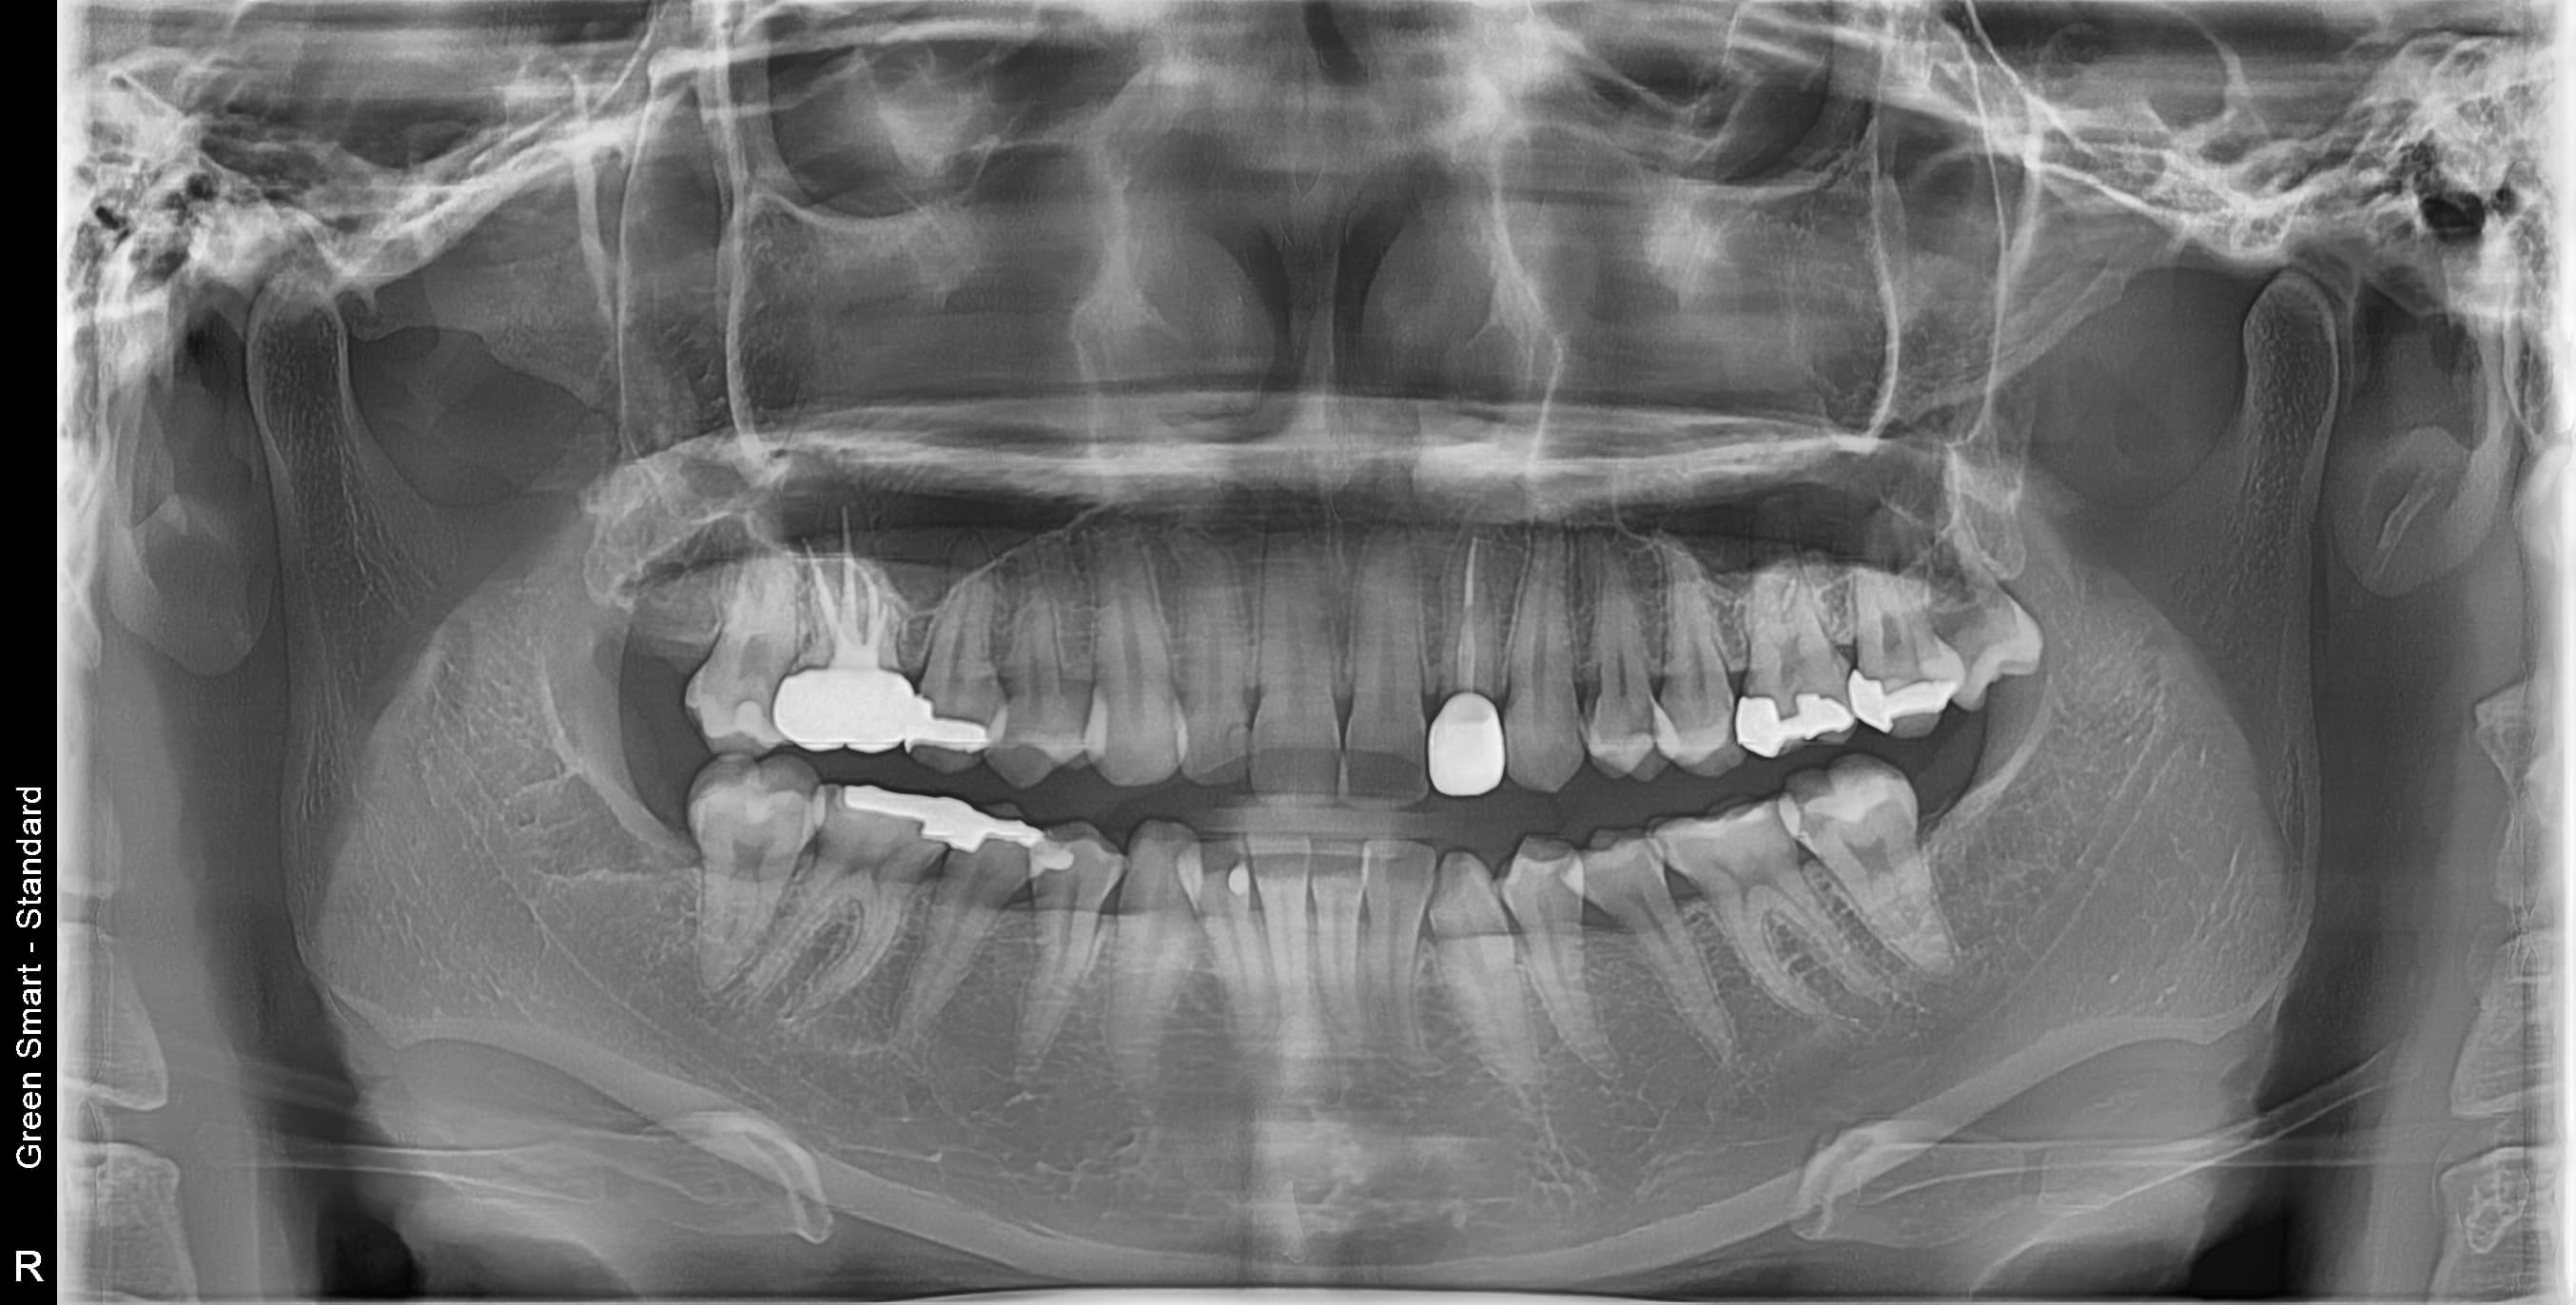

왜 지금 발치해야 할까요?

사랑니 방치 시 발생하는 문제

급성 염증

심한 통증과 얼굴 부종

인접 치아 충치

옆 치아까지 손상

턱관절 장애

만성 두통과 턱 통증

치열 불균형

교정 치료 필요